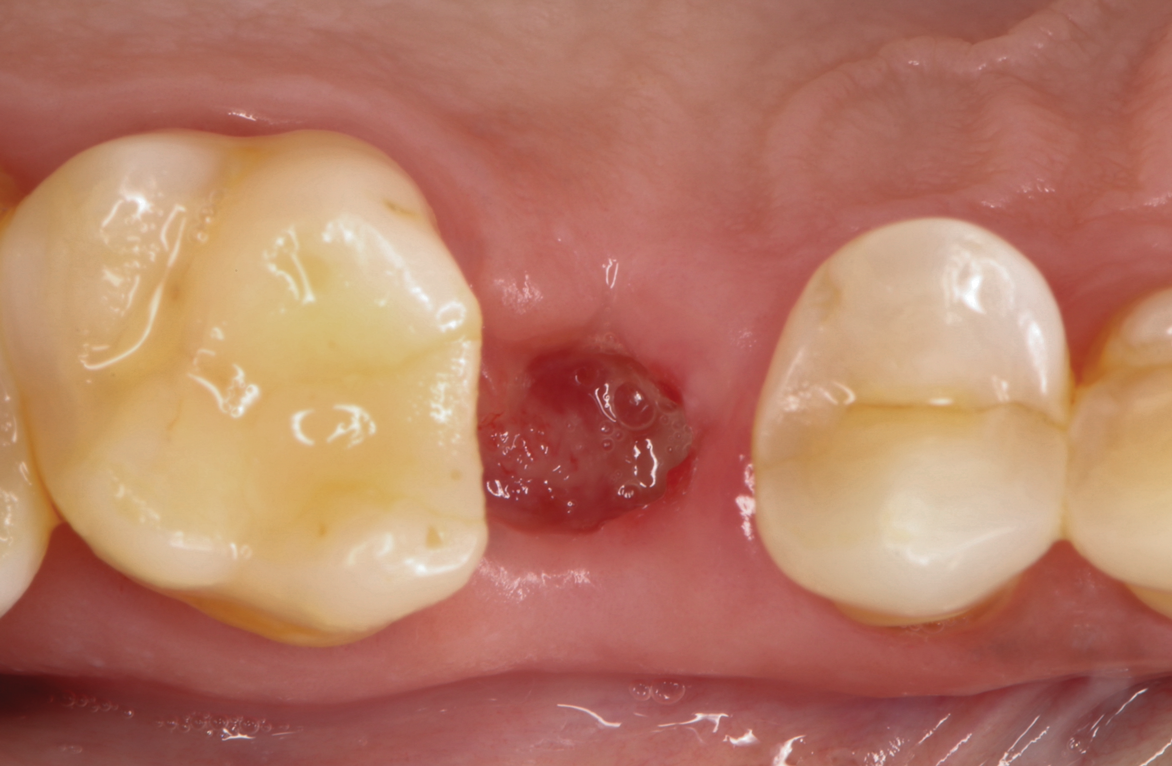

A regularly scheduled postoperative appointment 2 weeks after site preservation revealed adequate wound healing (Figure 6). The patient reported minimal to no discomfort and communicated that the cyanoacrylate layer had fallen out after 10 days, as expected, since the cyanoacrylate material acts as a dressing during early wound healing.

Fig 6. At 14 days, the protective cyanoacrylate seal had fallen out and adequate wound healing and a stable clot were observed. Soft-tissue granulation toward the center of the socket was evident.

Figure 6